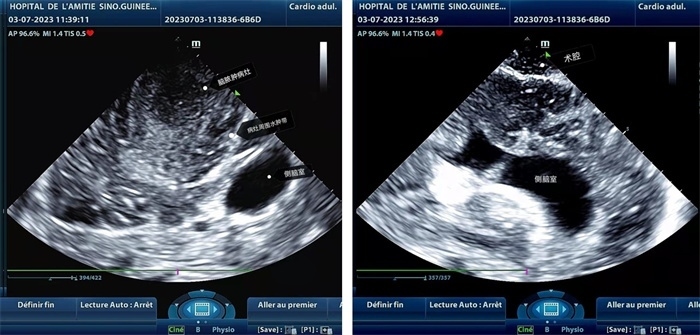

手術(shù)中,張國(guó)濱在超聲科顧秀娟的幫助下,運(yùn)用顱腦術(shù)中超聲技術(shù),通過(guò)將一次性保護(hù)套的超聲探頭置于腦組織表面,實(shí)時(shí)觀察病變的位置和形態(tài),進(jìn)一步確認(rèn)最佳手術(shù)路徑。術(shù)中超聲顯示,病變位于左額頂葉,大小約為4x4x3cm,邊界清晰,呈囊實(shí)性,周邊腦組織水腫明顯。最終,病灶順利切除,診斷為腦膿腫,并通過(guò)超聲檢測(cè)確認(rèn)術(shù)腔無(wú)病變殘留、無(wú)出血,為患者術(shù)后恢復(fù)提供了良好的保障。

左圖顯示術(shù)中超聲見(jiàn)囊實(shí)性病變,大小約為4x4x3cm,病灶周圍腦組織水腫明顯;右圖為病灶切除后,術(shù)中超聲示術(shù)腔無(wú)病變殘留

左圖顯示術(shù)中超聲見(jiàn)囊實(shí)性病變,大小約為4x4x3cm,病灶周圍腦組織水腫明顯;右圖為病灶切除后,術(shù)中超聲示術(shù)腔無(wú)病變殘留。中國(guó)第二十九批援幾內(nèi)亞醫(yī)療隊(duì)供圖